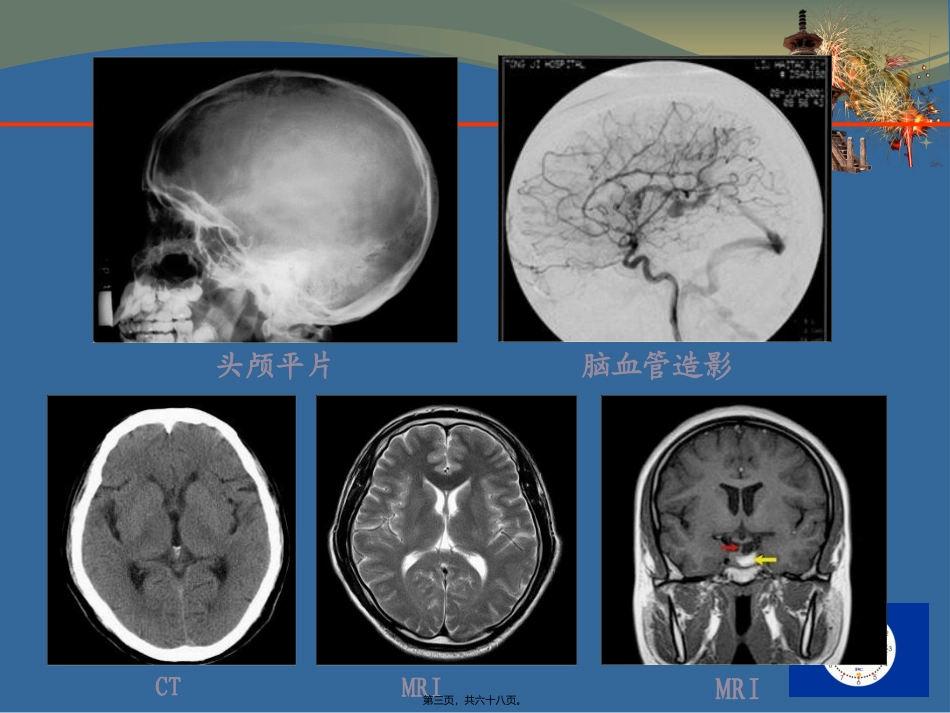

第一页,共六十八页。颅脑检查技术••••••••第二页,共六十八页。头颅平片脑血管造影CTMRIMRI第三页,共六十八页。正常脑CT横断位图像蝶鞍层面颅底层面第四页,共六十八页。正常脑CT横断位图像鞍上池层面三脑室前部层面第五页,共六十八页。三脑室后部层面侧脑室体部层面正常脑CT横断位图像第六页,共六十八页。侧脑室顶部层面脑室上层面正常脑CT横断位图像第七页,共六十八页。正常脑CT横断位图像骨窗第八页,共六十八页。正常脑MRI表现•横断位、矢状位、冠状位MRI像–清晰而逼真地显示–脑皮质、髓质、脑脊液–颅神经和脂肪–无骨骼伪影的干拢•MRI矢状位–脑干、中脑、桥脑、延髓•垂体柄和垂体–垂体正常高度为2-8mm第九页,共六十八页。正常脑MRI表现T1WIT1WIT1WIT2WIT2WIT2WI第十页,共六十八页。矢状位冠状位正常脑MRI表现第十一页,共六十八页。颅脑根本病变影像表现•平片〔颅内肿瘤定位征、颅高压征〕•脑血管造影〔颅内占位病变使脑血管受压移位、聚集或者别离,牵直或者扭曲〕•CTandMRI•病灶显示CT异常密度或MRI异常信号•病灶的强化表现•脑水肿〔brainedema〕•占位效应〔spaceoccupingeffect〕•脑积水〔hydrocephalus〕•脑萎缩〔brainatrophy〕第十二页,共六十八页。颅内肿瘤第十三页,共六十八页。胶质瘤〔Glioma〕•起源于神经胶质细胞•〔一〕星形细胞瘤〔astrocytoma〕•Ⅰ级分化良好,良性•Ⅱ级良恶性交界性肿瘤•Ⅲ-Ⅳ级分化不良,恶性第十四页,共六十八页。胶质瘤的MRI和CT表现CTMRI病理中心低密度T1低T2高坏死环形增强环形增强多血管性周围水肿T1T2延长血管源性水肿第十五页,共六十八页。胶质瘤〔Glioma〕•良性星形细胞瘤–影像学表现•均匀•无水肿无强化•CT低密度•MRIT1低信号T2高信号第十六页,共六十八页。胶质瘤〔Glioma〕•恶性星形细胞瘤•影像学表现•不均匀性•血管源性水肿•增强•不规那么血管第十七页,共六十八页。胶质瘤〔Glioma〕•恶性星形细胞瘤〔Ⅳ级〕•特点•三带-低密度中心、环形增强、水肿CT增强CT密度不均匀弧形、轮状分叶、水肿不规则厚环坏死、出血坏死、出血"囊状"、钙化中心不增强第十八页,共六十八页。胶质瘤〔Glioma〕第十九页,共六十八页。星形细胞瘤的多形性第二十页,共六十八页。良性星形细胞瘤(29-year-oldfemale)T1WIT2WICET1WI第二十一页,共六十八页。恶性星形细胞瘤瘤(45-year-oldfemale)T1WIT2WICET1WI第二十二页,共六十八页。少突胶质细胞瘤〔Oligodendroglioma〕CTMRI等、低、高密度T1等、低轻或中度强化轻或中度强化占位效应相对轻占位效应相对轻水肿轻微水肿轻微钙化(70%)T2高、低信号囊变少见囊变少见颅内最易发生钙化的肿瘤第二十三页,共六十八页。少突胶质细胞瘤〔Oligodendroglioma〕T1WIT2WICET1WI第二十四页,共六十八页。髓母细胞瘤〔medulloblastoma〕CTMRI小脑蚓部高密度或等密度肿块T1WI呈低或等信号T2WI呈等或高信号密度不均信号强度不均匀钙化、囊变、坏死、出血肿瘤周围轻度水肿增强为不均匀强化增强为不均匀强化四脑室受压、脑积水四脑室受压、脑积水第二十五页,共六十八页。髓母细胞瘤(14-years-oldmale)第二十六页,共六十八页。髓母细胞瘤(14-years-oldmale)第二十七页,共六十八页。髓母细胞瘤MRIT1WICET1WI第二十八页,共六十八页。T1WICET1WI髓母细胞瘤MRI〔接上〕第二十九页,共六十八页。脑膜瘤〔meningioma〕•脑外肿瘤•脑膜瘤起源于蛛网膜粒细胞•好发部位依次为–矢状窦旁大脑凸面大脑镰嗅沟–鞍结节蝶骨嵴小脑桥脑角–小脑幕斜坡第三十页,共六十八页。脑膜瘤X线表现•头颅平片•邻近颅骨可见颅骨内外板变薄、膨胀、吸收•有骨质增生、硬化•颅板增厚等改变•血管造影•血供丰富•肿瘤均匀一致和持续强化•即为“肿瘤染色〞第三十一页,共六十八页。脑膜瘤CT表现•平扫–多表现为均匀略高密度或低密度–结节或肿块影–肿瘤钙化发生率约为15%•增强–肿瘤常明显均匀强化–轮廓光滑整齐–瘤周低密度区,边界清楚•脑外起源征象–白质坍陷征、脑膜强化–颅骨增生、硬化,破坏或变薄第三十二页,共六十八页。脑膜瘤MRI表现•T1WI上等信号•T2WI上多为等、...